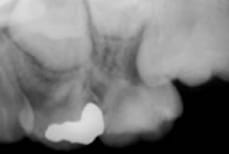

6歳臼歯が手前の乳臼歯にひっかかり、スムーズに生えてこない場合があります。正常な位置とは異なった位置に生えようとすることから「異所萌出」といいます。

そのままにしておくと、ひっかかっている乳臼歯の根は吸収して早期に抜けてしまいます。6歳臼歯は本来の位置よりも前方に生え、乳臼歯の後に続く永久歯の萌出スペースがなくなってしまいます。6歳臼歯は咬み合わせの要になる重要な歯です。6歳臼歯の咬み合わせに問題が生じると、その後の歯ならびや全体的な咬み合わせにも影響を与えてしまいます。

6歳臼歯の異所萌出が認められた場合、金具やゴムを使って、正しい位置に誘導します。

6歳臼歯が手前の乳歯にひっかかり、根を吸収しています。

歯に小さいバネを付けて、6歳臼歯を正しい位置まで誘導しました。